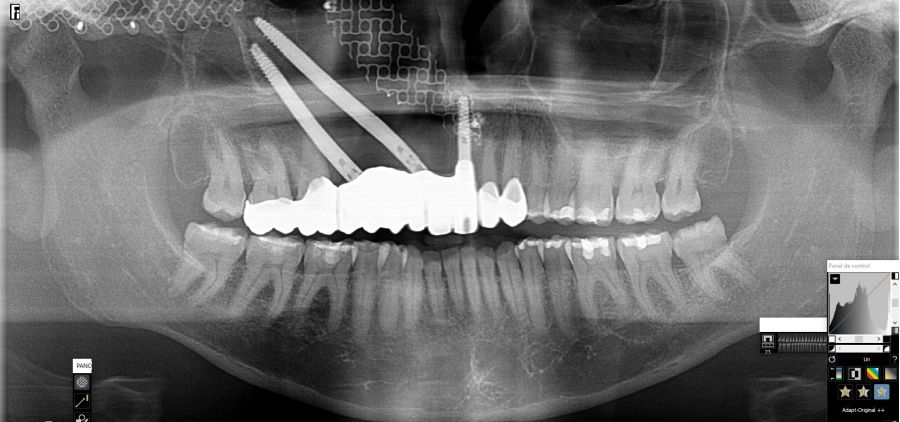

Presentamos el caso de una paciente de 47 años que acude al servicio de cirugía maxilofacial por dolor en el área sinusal derecha en Junio de 2020. Se realizó una radiografía panorámica en la que se observó una imagen sospechosa en la zona del primer cuadrante. Dichos hallazgos se confirmaron con la realización de una tomografía axial computarizada (TAC) facial y una resonancia magnética en las que se identifica una extensa lesión tumoral que ocupaba el seno maxilar derecho e infiltraba el suelo de la órbita derecha y fosa nasal derecha (Figuras 1, 2 y 3). Tras la realización de una biopsia, se confirmó la presencia de un carcinoma adenoide quístico. De este modo, se planificó la extirpación quirúrgica y la fijación mediante placas preformadas sobre un modelo impreso en poliamida (Figura 4).

Bajo anestesia general, se realizó la resección quirúrgica junto con la fijación de dos placas preformadas y colocación simultánea de dos implantes cigomáticos y un implante endoóseo en posición del 2.1 (Figuras 5 y 6). Debido a la presencia de márgenes quirúrgicos comprometidos en el informe anatomopatológico, se indicó la administración de radioterapia adyuvante. Por este motivo, se decidió realizar un puente provisional dentosoportado de 1.7 a 2.3 (Figura 7) para mejorar la situación estética y funcional de la paciente durante todo el proceso y evitar un colapso de los tejidos blandos por la radioterapia. Para ello, se tallaron los molares (1.7, 1.6) e incisivo lateral y canino (2.2, 2.3), y se fabricó un puente fresado en polimetilmetacrilato (PMMA) con refuerzo metálico (Figuras 8 y 9).